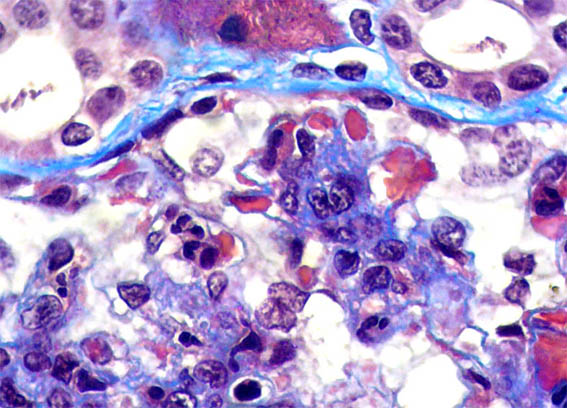

Figura 6.

Tricrómico de Masson, X1.000.